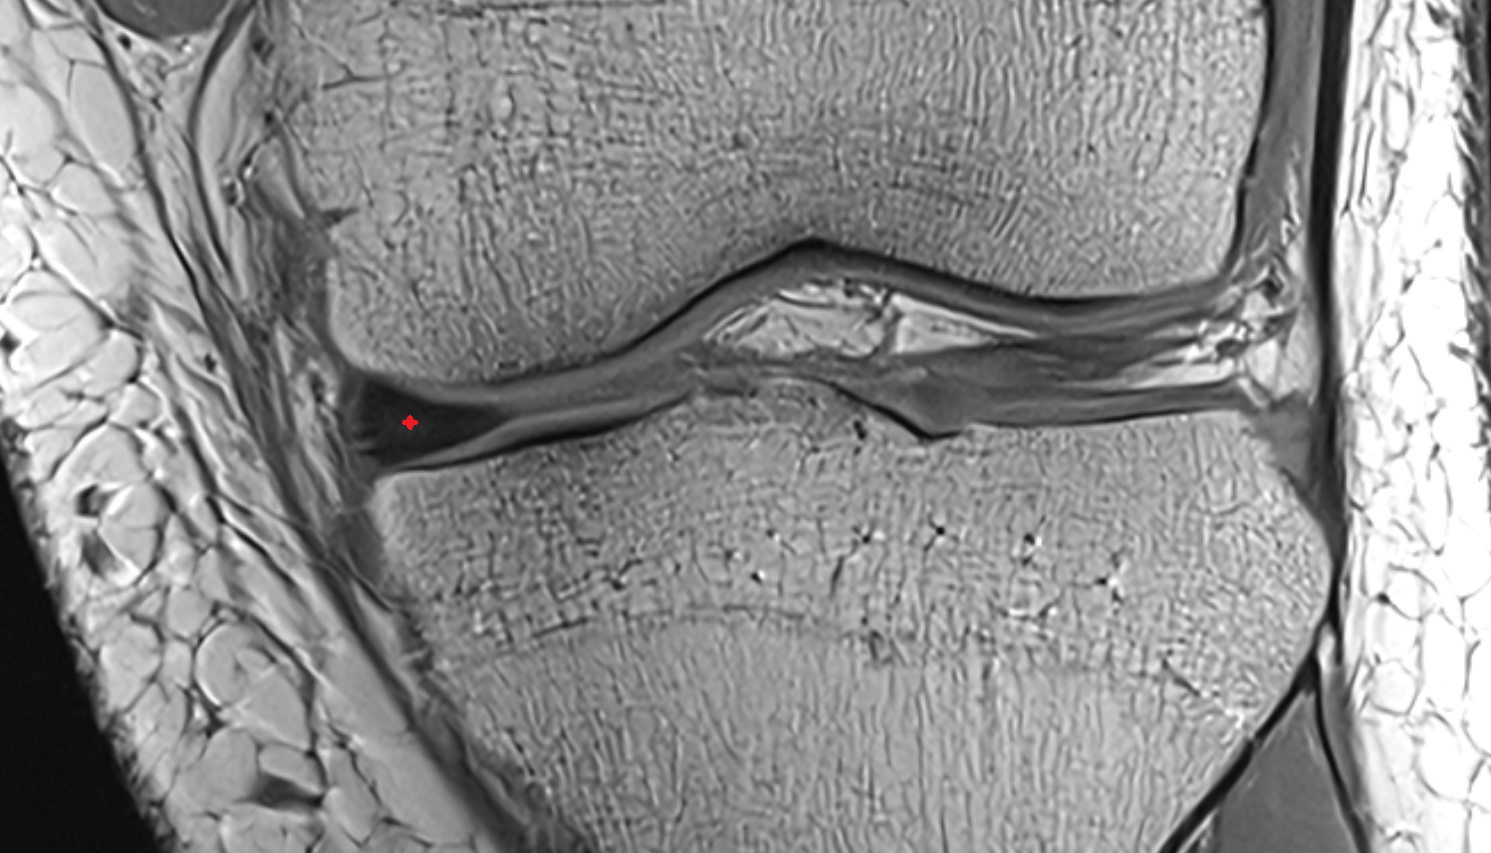

- Medial collateral ligament

- Medial meniscus

- Body of medial meniscus

- Anterior root of medial meniscus